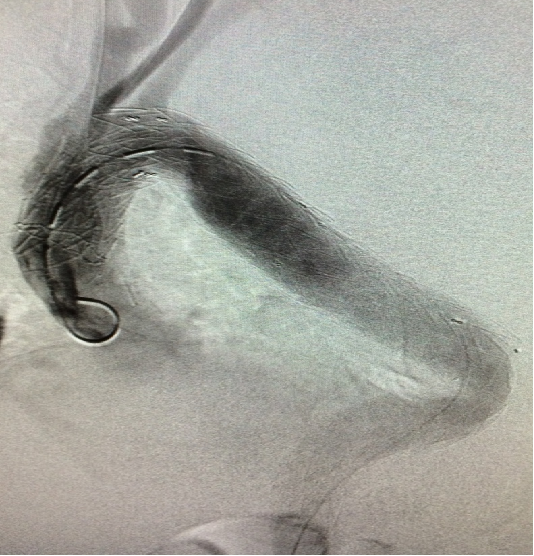

▎病例四

男, 49岁,急性夹层 。2018年11月TEVAR。一月后复查:RTAD 。 2019年1月双开窗。2019年4月2日 复查,结果良好。